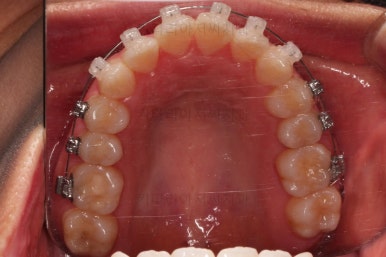

이번 환자분이 선택하신 장치는 데이몬 클리어라고 하는 자가결찰 세라믹 장치인데요.

데이몬 클리어는 현재 사용되는 세라믹 장치 중에 가장 심미성이 뛰어난 장치입니다.

흔히 세라믹 장치로 많이 아시는 클리피씨, 엠파워 클리어 등을 철사를 잡아주는 캡이 메탈로 되어 있어 유심히 관찰하면 메탈 부분이 있는 반면에 데이몬 클리어는 캡 자체도 세라믹으로 되어있어 심미성이 좋습니다.

다만, 통 바디 형태의 세라믹으로 되어있다 보니 강도 증가를 위해서 부피가 약간 더 커진 단점은 있습니다.

상하좌우 총 4개의 미니스크류를 이용해서 치열을 뒤로 당겨줍니다.

중간평가를 하면서 환자분과 가능한 수준/원하는 수준을 잘 조율해 가면서 입매를 정해갑니다.